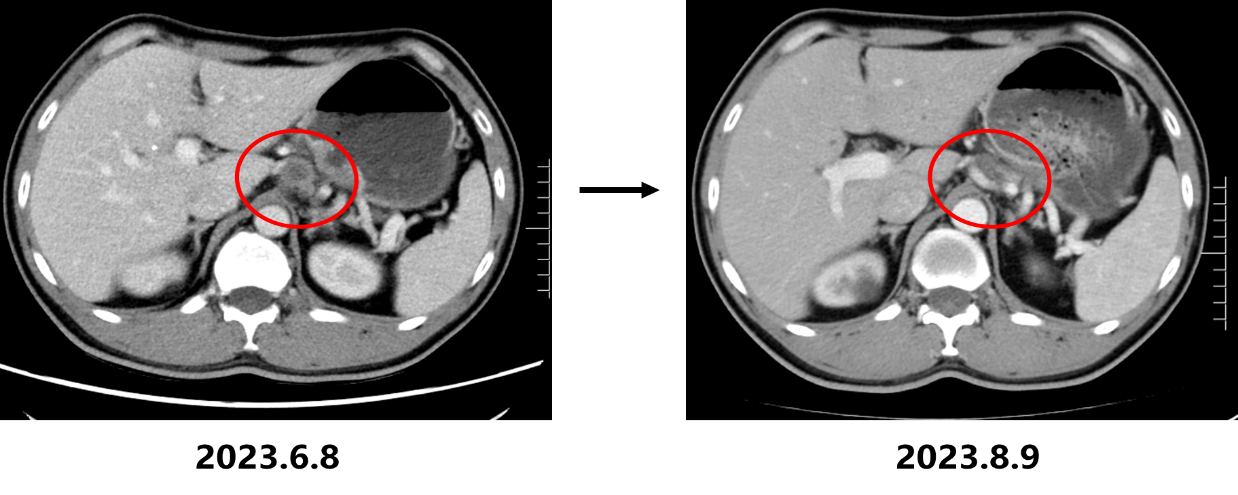

• 2023.8.10复查CT:胃底贲门部胃壁增厚明显改善,肝胃间隙及腹膜后多发淋巴结转移瘤较前缩小(大者短径17mm)、双肺多发转移瘤较前缩小、减少,疗效评估为部分缓解(PR)。